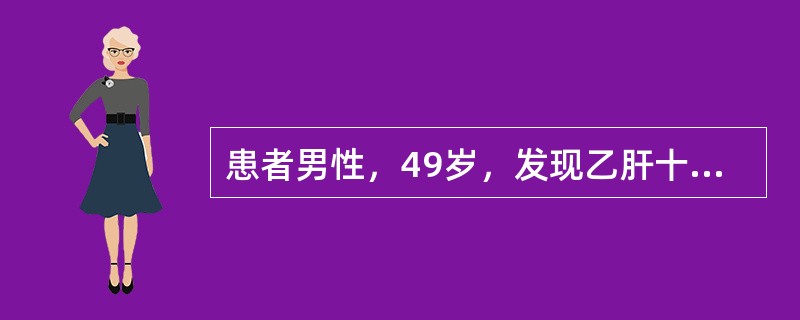

患者男性,49岁,发现乙肝十余年,反复腹痛,腹胀黄疸月余,CT图像如下,最有可能的诊断是( )。

CT平扫

[单选题]患者男性,49岁,发现乙肝十余年,反复腹痛,腹胀黄疸月余,CT图像如下,最有可能的诊断是( )。CT平扫动脉期增强门静脉期增强A.肝肉瘤B.肝血管瘤

[单选题]患者男性,49岁,发现乙肝十余年,反复腹痛,腹胀黄疸月余,CT图像如下,最有可能的诊断是( )。CT平扫动脉期增强门静脉期增强A.肝肉瘤B.肝血管瘤

[单选题]患者男,49岁。发现乙肝十余年,反复腹痛,腹胀黄疸1个月余,CT图像如下,最有可能的诊断是A.肝血管瘤B.肝再生结节C.肝癌D.肝肉瘤E.肝腺瘤

[单选题,A2型题,A1/A2型题] 患者男性,49岁,发现乙肝十余年,反复腹痛,腹胀黄疸月余,CT图像如下,最有可能的诊断是()。A . 肝肉瘤B . 肝血管瘤C . 肝癌D . 肝再生结节E . 肝腺瘤

[单选题]患者男性,49岁,发现乙肝十余年,反复腹痛,腹胀黄疸月余,CT图像如下,最有可能的诊断是( )。A.肝肉瘤B.肝血管瘤C.肝癌D.肝再生结节E.肝腺瘤

[单选题]患者男性,49岁,发现乙肝十余年,反复腹痛,腹胀黄疸1个月余,CT图像如下,最有可能的诊断是()A.肝血管瘤B.肝再生结节C.肝癌D.肝肉瘤E.肝腺瘤

[单选题]患者男性,49岁,发现乙肝十余年,反复腹痛,腹胀黄疸1个月余,CT图像如下,最有可能的诊断是()。A . 肝血管瘤B . 肝再生结节C . 肝癌D . 肝肉瘤E . 肝腺瘤